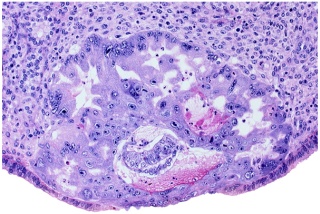

IntroductionStage 5b specimens have an estimated postfertilization age of 9 days with a conceptus diameter of approximately 0.1 mm. The distinguishing characteristic at this substage is the presence of numerous irregular, slit like lacunae within the cytoplasm of the syncytiotrophoblast. Most of the lacunae communicate with each other and with the endometrial sinusoids but they contain relatively little maternal blood. Read more... |